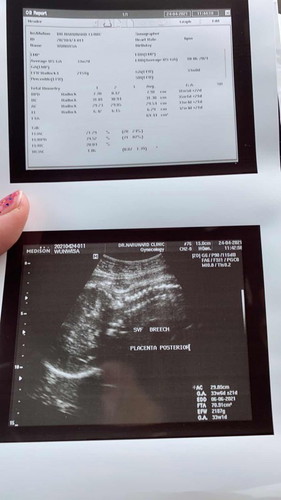

35 วีคแล้วยังไม่กลับหัว หัวน้องยังอยู่ใต้ราวนมแม่ หมอบอกมีโอกาสได้ผ่าสูง รออีกสองอาทิตย์อัลตร้าซาวด์อีกรอบ ใครมีประสบการณ์บ้างคะ